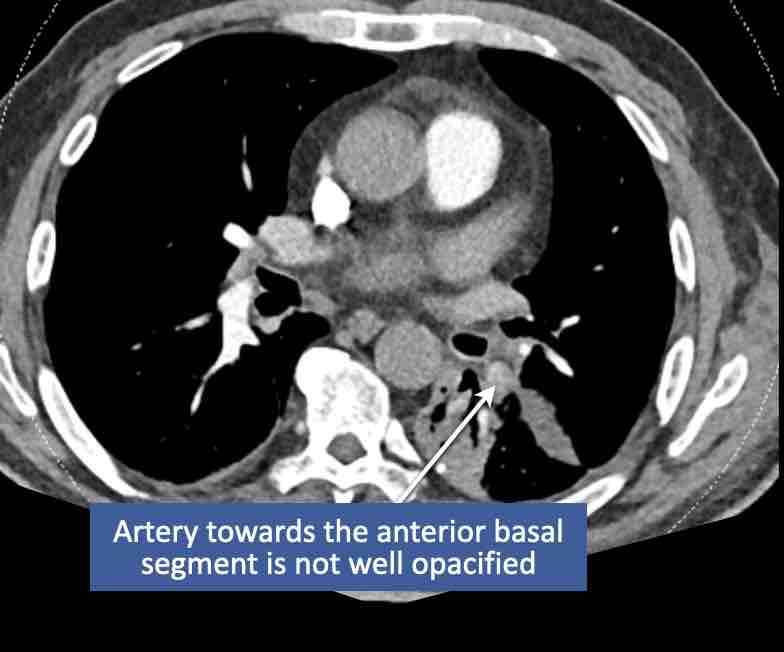

Hình ảnh

Cuộn qua các hình ảnh.

Theo dõi các phế quản của thùy dưới phổi trái cho thấy nhánh phân thùy đầu tiên của thùy dưới phổi trái còn thông; đó là phế quản phân thùy đỉnh.

Các ghim phẫu thuật nằm tại vị trí của các phân thùy đáy sau và đáy bên (LB9/10), vốn thường được cắt bỏ cùng nhau.

Do đó, phân thùy phổi có hình ảnh kính mờ và đông đặc phải là phân thùy đáy trước của thùy dưới phổi trái (LB8).

Động mạch phổi đến phân thùy này cũng không ngấm thuốc cản quang, và bản đồ tưới máu iốt nhấn mạnh thêm tình trạng nhồi máu.

Bệnh nhân đã được phẫu thuật lại và tiến hành cắt bỏ phân thùy bị nhồi máu, với xác nhận qua giải phẫu bệnh.

Trên bản đồ tưới máu iốt, có sự tưới máu ở thùy trên phổi trái và phân thùy đỉnh của thùy dưới phổi trái, nhưng không có sự tưới máu ở phân thùy đáy trước của thùy dưới phổi trái.